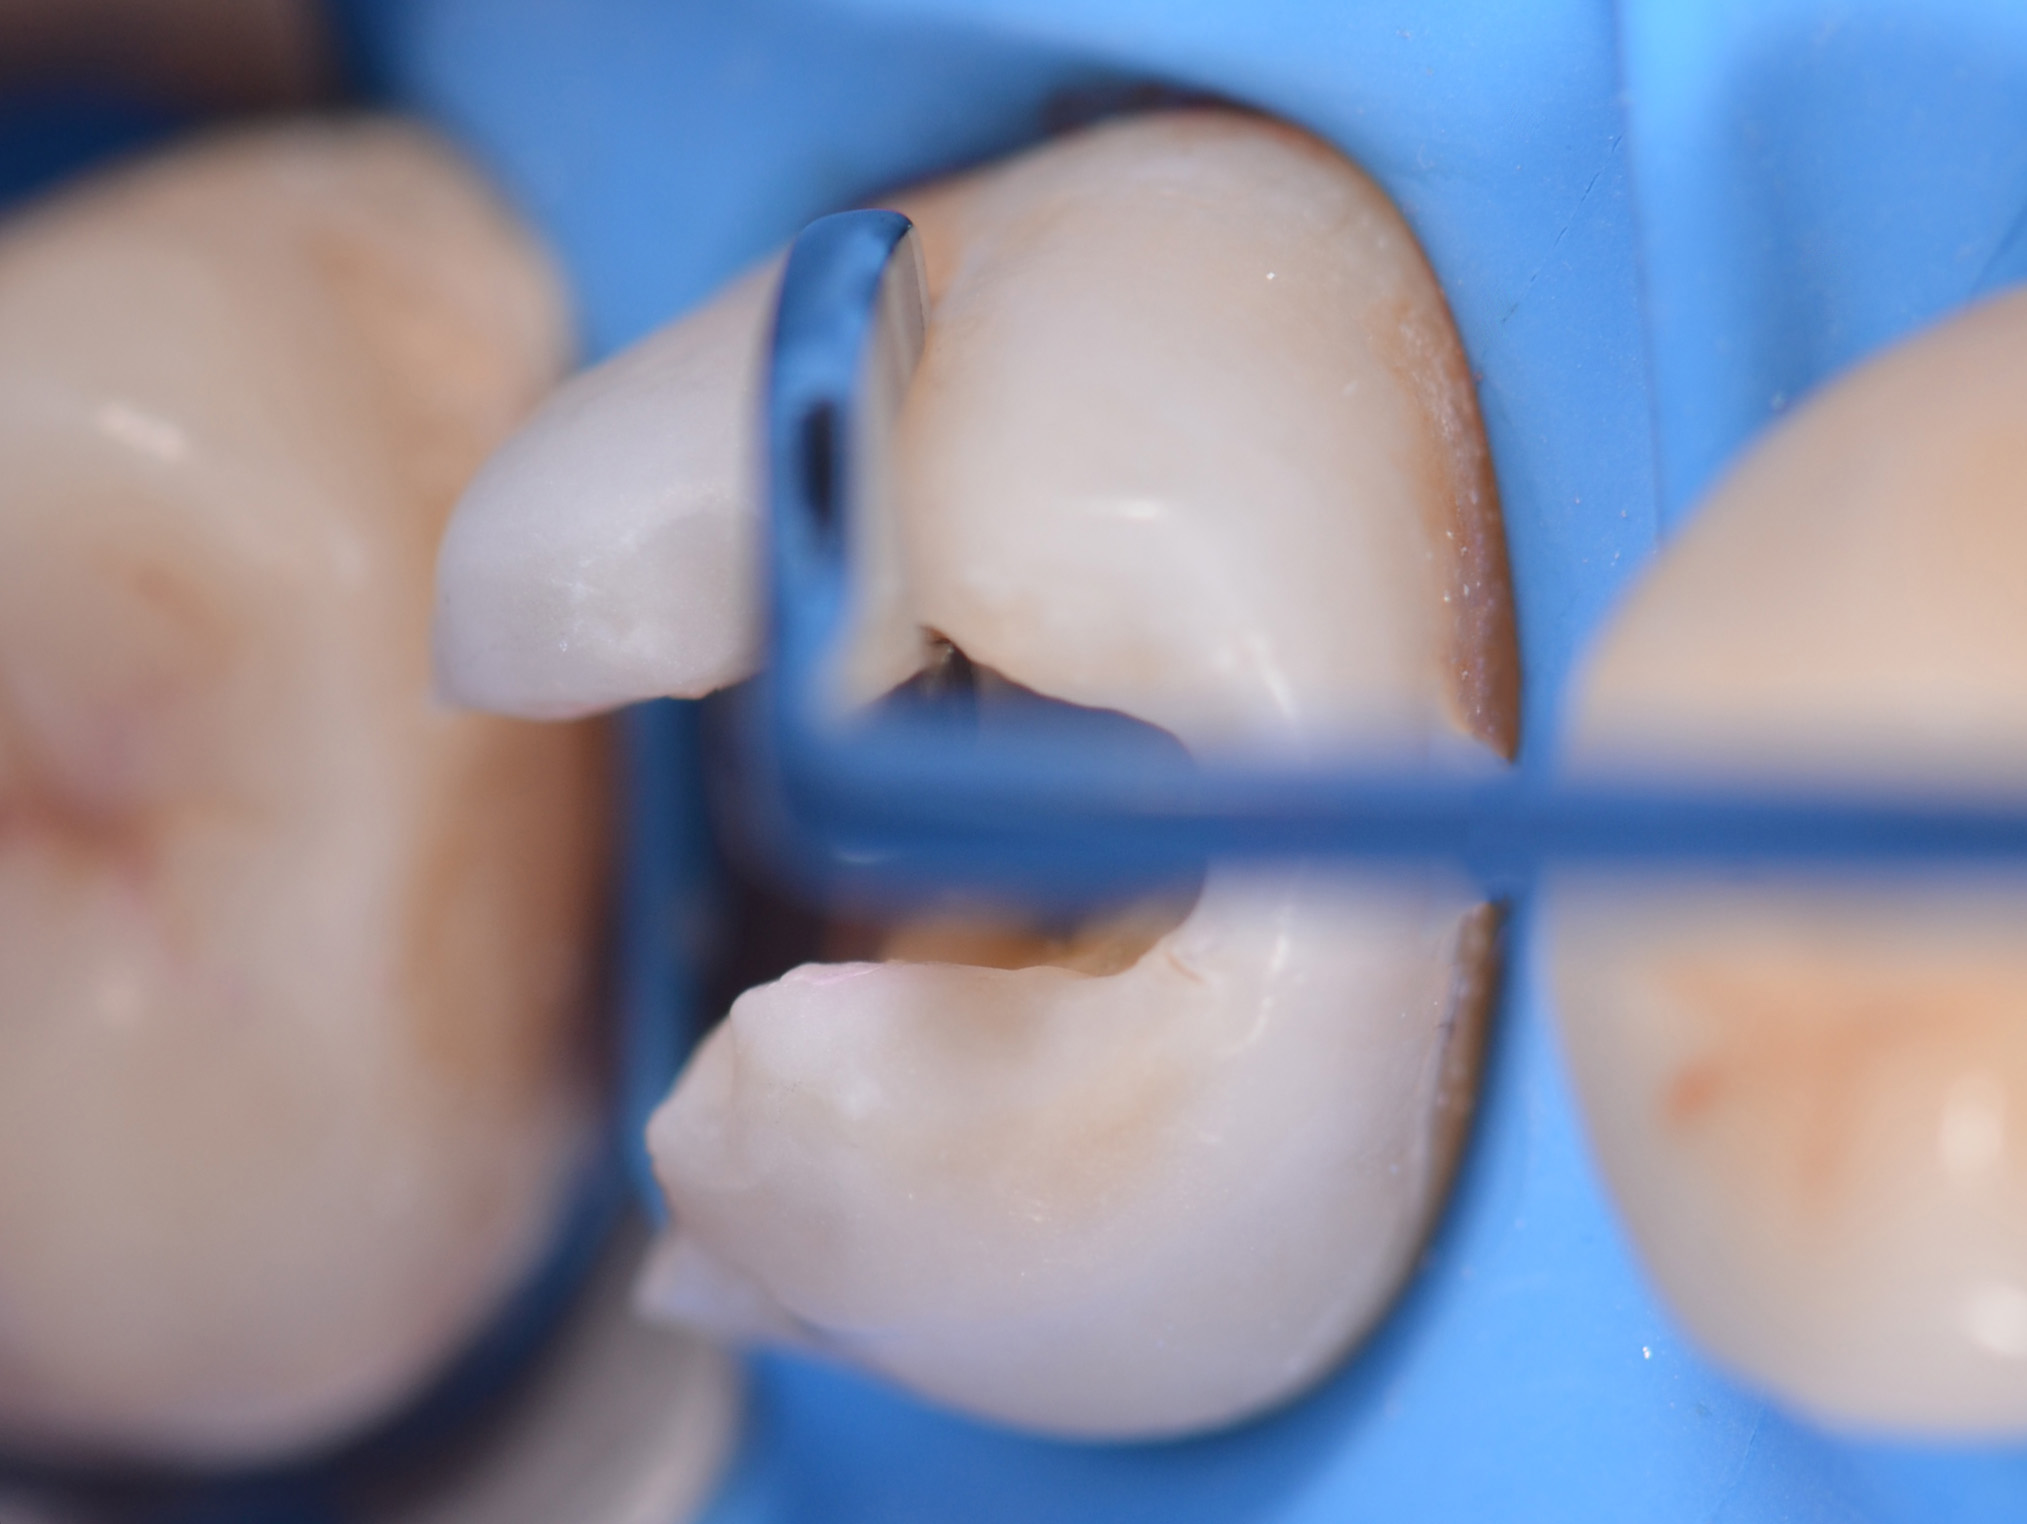

Una volta completata la rimozione della carie, si inserisce un cuneo interdentale (Composi-Tight 3D Fusion, Garrison) e si posiziona una matrice sezionale con anello di contenimento dello stesso sistema per ricostruire la parete distale.

La rilocazione del margine viene eseguita mediante un build-up periferico con composito opaco (7, 8) (Brilliant, Coltene, Altstätten, Svizzera).

Preparazione cavitaria per onlay

In un unico step si realizza la preparazione del box distale per l’onlay, eliminando la porzione distale del restauro. La sequenza prevede:

- riduzione del piano occlusale con fresa tronco-conica a testa arrotondata;

- preparazione dell’istmo occlusale;

- realizzazione dei box prossimali con fresa tronco-conica a testa piatta;

- svasatura distale con frese a fiamma (carburo di tungsteno e diamantate). Le pareti del box devono essere leggermente divergenti in senso occlusale (angolo di circa 4°) e non eccedere i 2 mm di spessore;

- arrotondamento dei bordi con fresa in pietra di Arkansas e gommino (Figura 8).